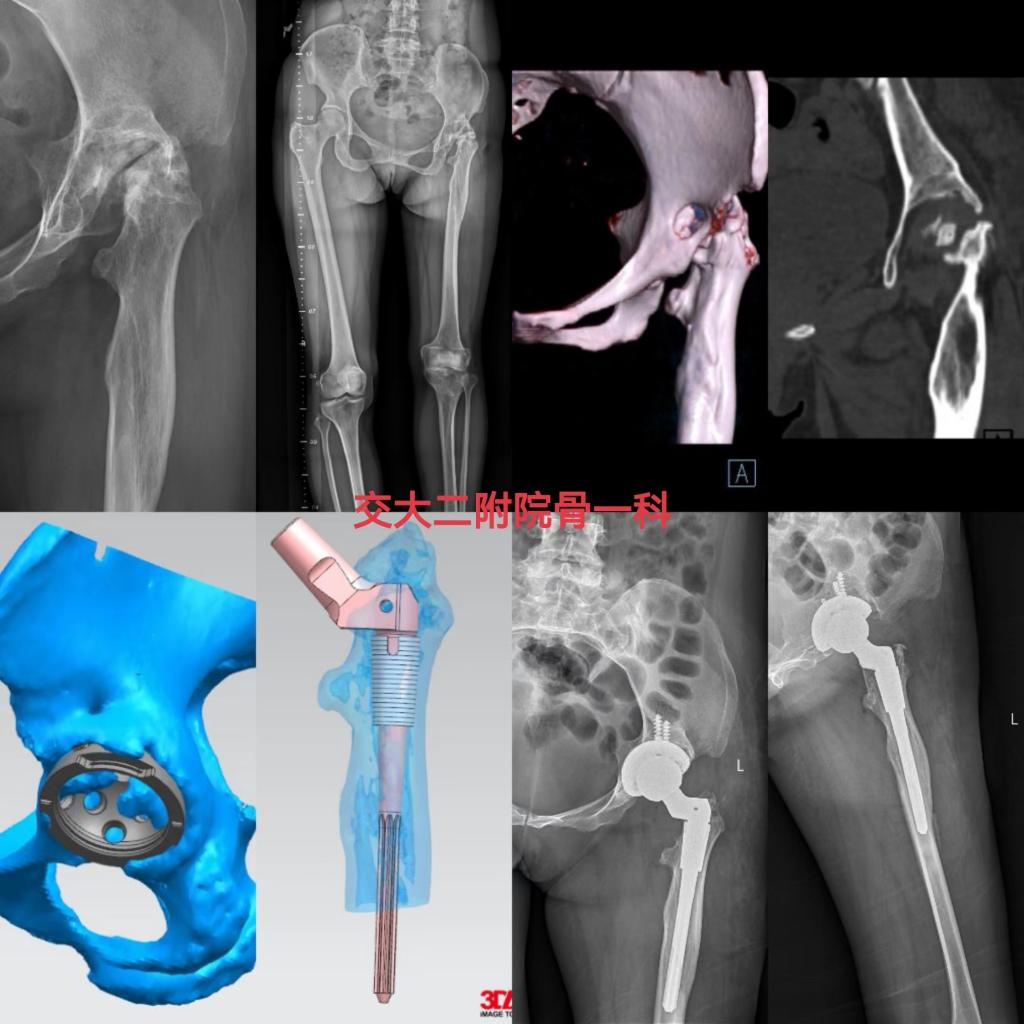

骨一科还成功完成多例髋关节置换术。一位中年女性患者以“左髋疼痛伴跛行30余年”入院,诊断为左髋关节感染后关节屈曲挛缩畸形,左下肢短缩(约10cm),完善相关检查排除手术禁忌后,由党晓谦主任主刀完成左髋关节置换手术,术后恢复良好,已顺利出院。

一位患者摔伤后左髋部疼痛活动受限3天,诊断为左侧股骨颈骨折(Garden Ⅳ型),骨质疏松症,癫痫,完善相关检查排除手术禁忌后,由时志斌副主任主刀完成我院首例左髋关节置换术(AK-Ringfix限制性假体),术后恢复良好,已顺利出院。